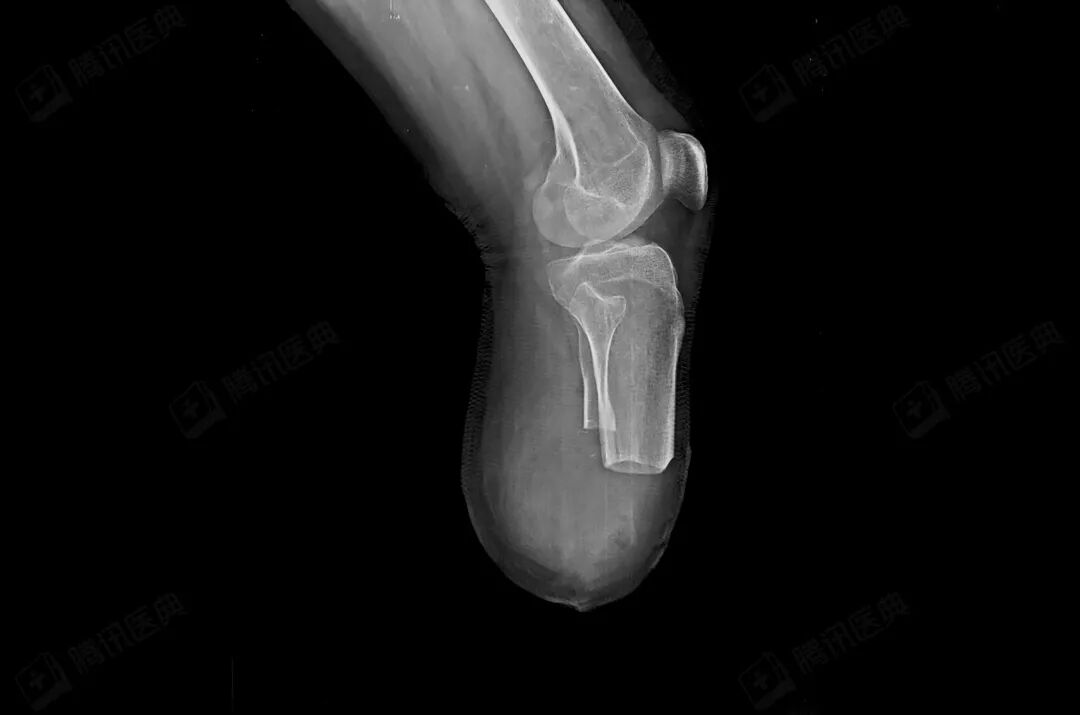

孙淑琴和吴喜飞的心情再次跌入谷底。松松腿部感染很严重,从外面看已烂掉,医生建议截肢保命,不截肢就无法化疗,控制不了疯长的肺部肿瘤。

后来医生跟松松谈了一次话,他终于同意截肢。4月16日,手术醒来后,看到右小腿没了,松松撕心裂肺地哭喊:“活着有什么意思,死了算了。”

截肢后,他戴过假肢,吃过靶向药,尝试过PD-1,但是都失败了,肺内的肿瘤在进展加重。